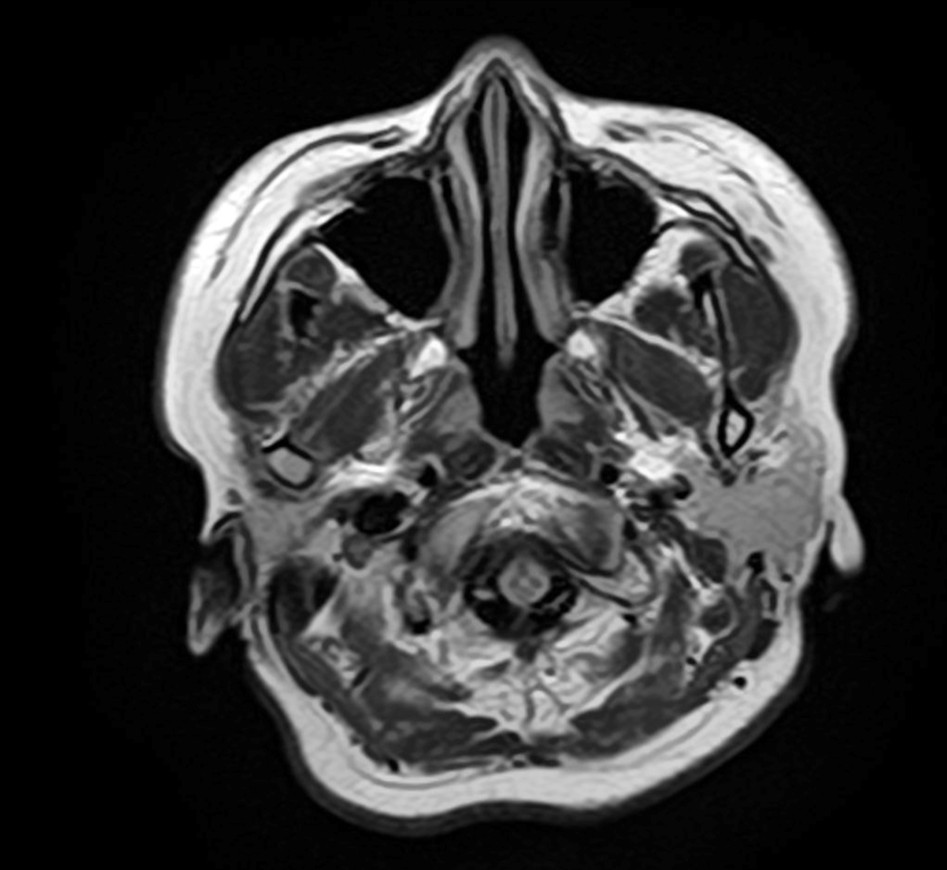

4.【画像解説】MRIでわかる副鼻腔炎と脳の状態

当院では、頭痛の原因を特定するためにMRI検査を実施しています。

正常 副鼻腔 MRI

正常な上顎洞

副鼻腔炎MRI画像

膿がたまっている上顎洞

目の下・周囲の痛みの原因

正常な前頭洞

膿がたまっている前頭同

眉間の痛みの原因

MRI検査の最大のメリットは、「鼻が原因の頭痛」と「脳疾患が原因の頭痛」を一度の検査で同時に、かつ詳細に判別できる点にあります。

【MRIでどこを見るのか】

MRI画像では、脳や脳血管はもちろん、鼻の奥にある空洞を精査します。

健康な状態: 空気が入っているため、炭のように「真っ黒」に映ります。

副鼻腔炎の状態: 膿や粘膜の腫れがある部分は、「白く濁った雲」のように映し出されます。